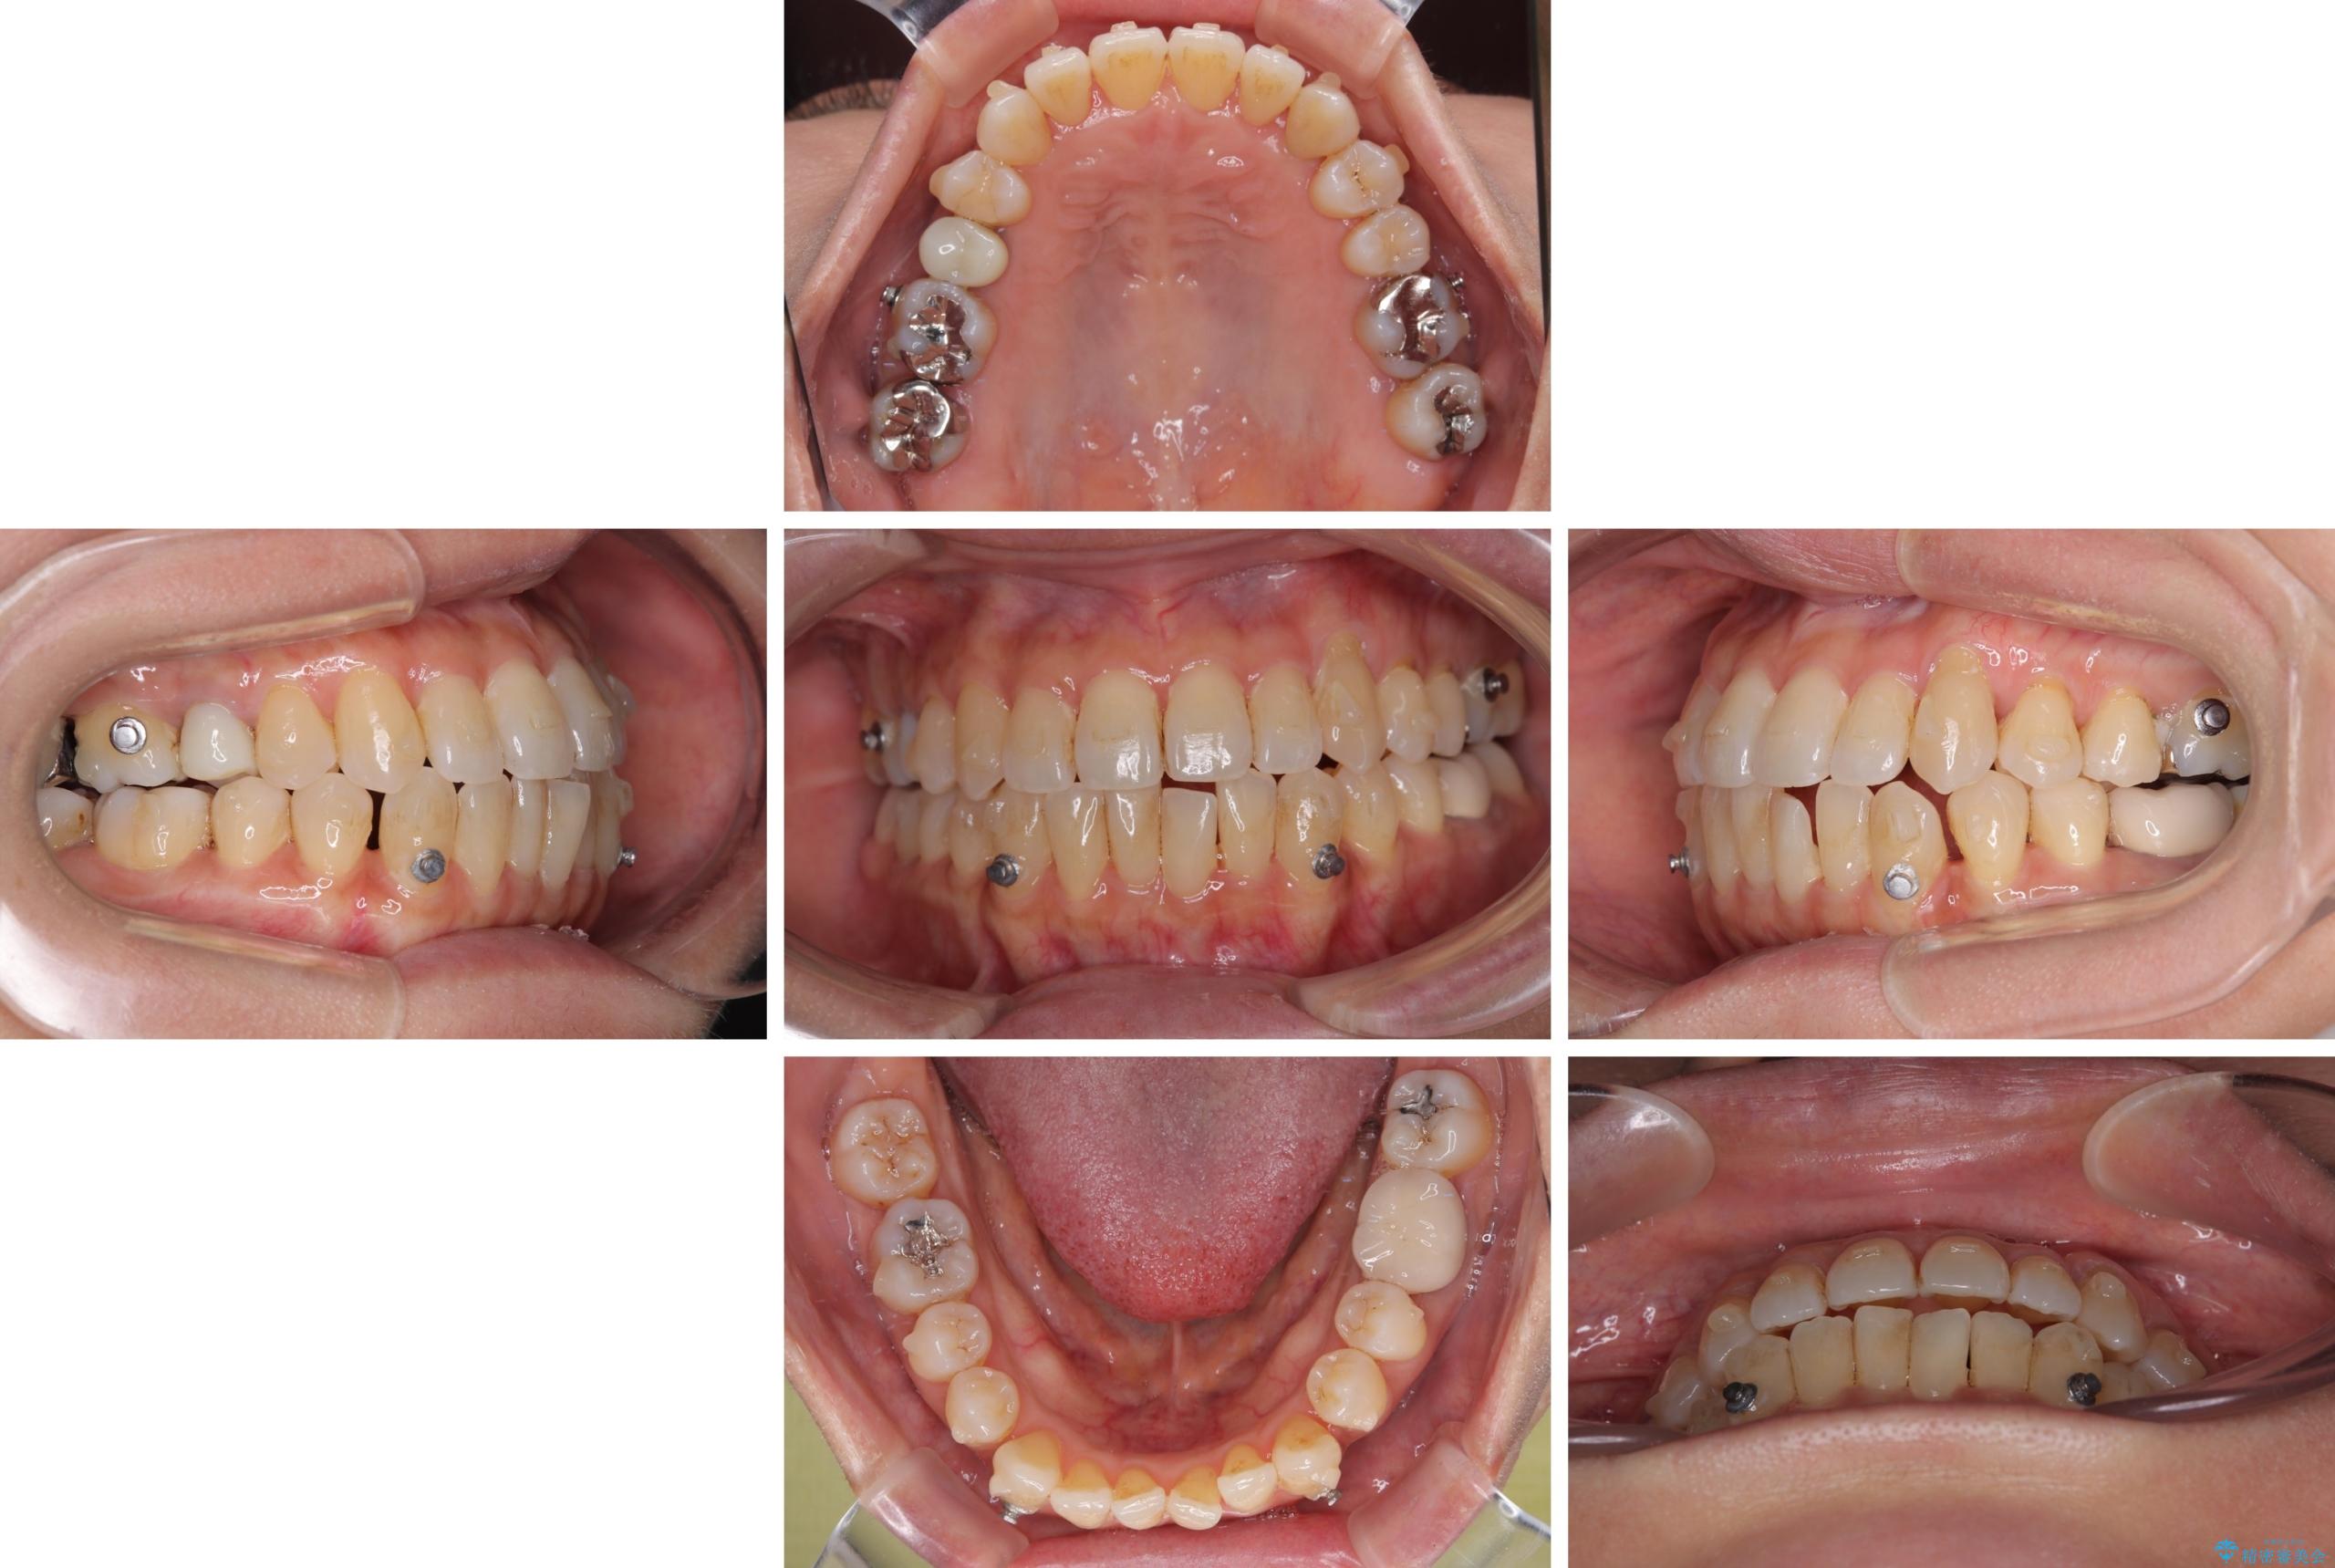

受け口と八重歯を改善 インビザライン矯正治療

- 前歯のデコボコや八重歯を治したいとのことで来院された患者様です。

受け口傾向の骨格であり、前歯はクロスバイトまたは切端咬合となっており、下顎を中心に歯列全体の後方移動を行い、IPR(歯と歯の間を削る)によってデコボコが解消するように設計し、インビザラインにより治療を行うこととしました。

受け口傾向のインビザライン矯正は比較的治療を行いやすいため、きれいに仕上げることができました。舌の突出癖が顕著であったため、改善のためのトレーニングをしっかりと行っていただきました。